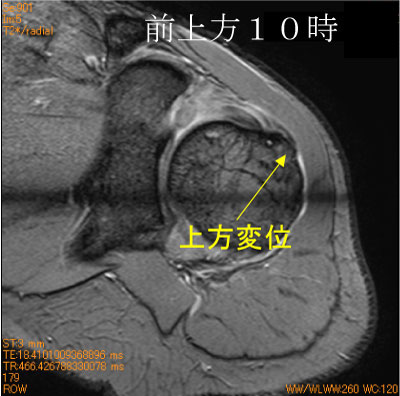

50代女性、自転車で転倒、単純撮影では見えない骨変化。

直達外力による骨損傷だが、安静が不十分だと腱板による牽引により上方に変位する。脂肪抑制T2 WI が有用。

骨挫傷部位は棘上筋腱が単独で付着するsuperior facet。

![]() Radial scan T2*WI 脂肪抑制 |